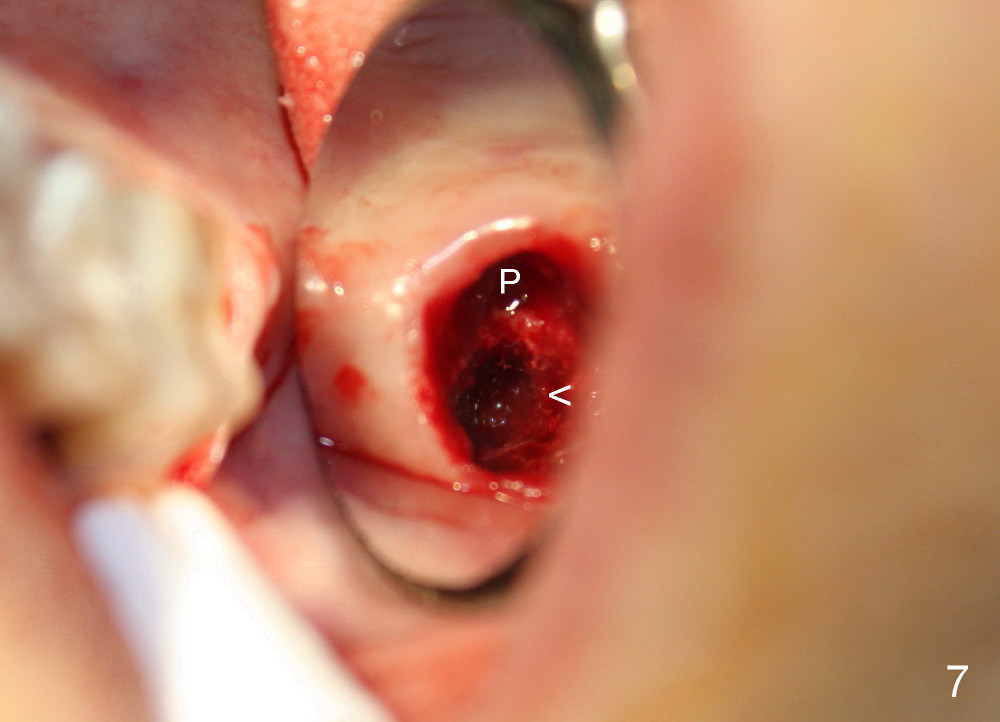

A 51-year-old lady has multiple restorations (Fig.1-3), e.g., amalgam (A in Fig.1) of the upper right 2nd molar as well as history of pulpotomy. The 1st molar has periapical radiolucency (* in Fig.1) and needs root canal therapy. The lower 3rd molar occludes (Fig.2 arrow) with the upper 2nd molar. The latter fractures subgingivally (Fig.3 <) and is extracted with a large MB root (Fig.4) and MB socket (Fig.5). The gingival one third of the palatal wall is defective, as indirectly indicated by granulation tissue palatally (Fig.5 <). So the osteotomy for the immediate implant will not be placed in the palatal socket. The septum is pointed coronally. The pointed portion of the septum is removed; initial osteotomy is formed by 1.5 mm pilot drill in the septum, followed by 2-5 mm osteotomes with the depth of 17 mm. The enlarging osteotomy is deviating buccally; drills are being used to move the osteoomy palatally without much success. When a 5 mm tap is inserted, it is stable and appears to be inside the maxillary sinus (Fig.6). In fact the osteotomy has bony walls around (Fig.7 <), including apical, when the tap is removed. Preop PA shows that the palatal root is apical to the sinus floor (Fig.1 between arrows).